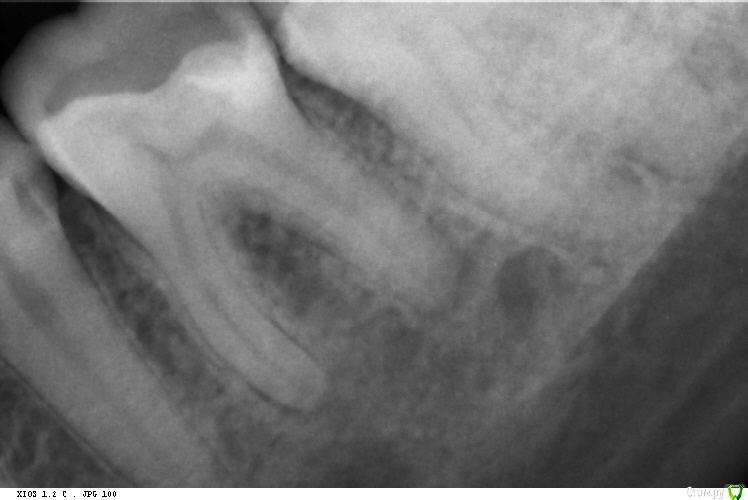

St. Опубликовано 29 октября, 2016 Автор Поделиться Опубликовано 29 октября, 2016 Реколл случая http://forum.stom.ru/topic/29857-endo/?p=529024. Прошло 11 месяцев после пломбировки)) 3 Ссылка на комментарий

Fred Опубликовано 29 октября, 2016 Поделиться Опубликовано 29 октября, 2016 Реколл случая http://forum.stom.ru/topic/29857-endo/?p=529024. Прошло 11 месяцев после пломбировки)) А почему такие жесточенные поры под реставрацией? Ссылка на комментарий

vse32 Опубликовано 29 октября, 2016 Поделиться Опубликовано 29 октября, 2016 А почему такие жесточенные поры под реставрацией? Может устья чем заливали, не контрастным. Свет, СИЦ? Ссылка на комментарий

St. Опубликовано 29 октября, 2016 Автор Поделиться Опубликовано 29 октября, 2016 (изменено) А почему такие жесточенные поры под реставрацией?Текучка градии нерентгенконтрастна. Как и сам материал большинства цветов. Керамика в планах. Ждали динамики. Изменено 29 октября, 2016 пользователем St. Ссылка на комментарий